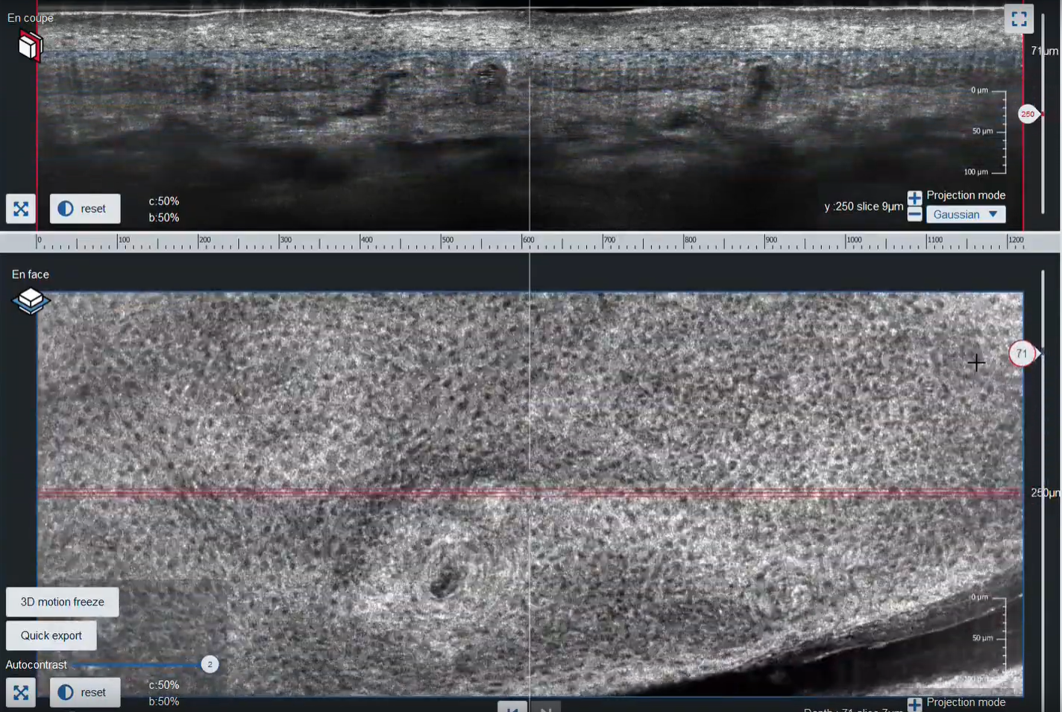

deepLive™ integrates LC-OCT (Line-field Confocal Optical Coherence Tomography) technology which provides a unique 3D imaging modality, allowing the user to switch from a histology-like vertical mode to a confocal-like horizontal mode,

and to record a 3D stack of tissue volumes in situ.

Navigations in LC-OCT™ 3D stacks

LC-OCT™ imaging of a fingerprint